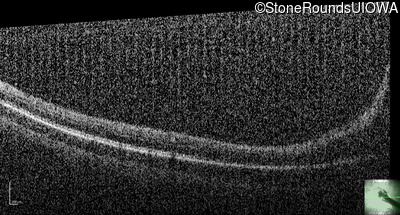

Optical Coherence Tomography - Right - 20/500

Exemplar / OCT Stack

Optical Coherence Tomography - Left - 20/300